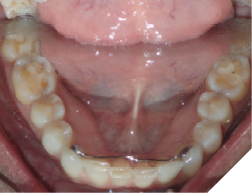

The majority of the orthodontic practices offer a period of “supervised retention” to their patients and communicates the customized retention recommendation with the patient’s general dentists. It is extremely important to work as a team to achieve long term clinical success in maintaining a functional bite and aesthetic smile. The general dentists continue to see their patients on a regular basis and have an opportunity to assess the orthodontic retainers and the bite after the supervised retention period is completed by the orthodontists. With great care, orthodontic retainers would serve for a long time (Fig. 1) without any major issues. However, in some cases, the failure to notice the clinical problems early on results in functional issues that would require a comprehensive orthodontic treatment to correct it (Fig. 2).

Fig. 2A

Fig. 2B

Fig. 2C